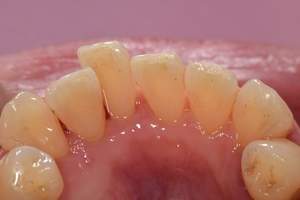

歯石除去

治療前

治療後

| 年齢 | 36歳・男性 |

| 主訴 | 歯石をとりたい |

| 治療内容 | 歯石除去 |

| 治療期間 | 30分 |

| 費用 | 約2,000円 |

| リスク・副作用 | ・歯ぐきの炎症が強いと歯石を取る際に出血することがあります。 ・処置後に歯がしみることがあります。 ・歯と歯の間に隙間ができるので、息が漏れ発音しにくいと感じることがあります。 ・歯ぐきの炎症が軽減すると歯ぐきが引き締まり、歯が長く見えることがあります。 |